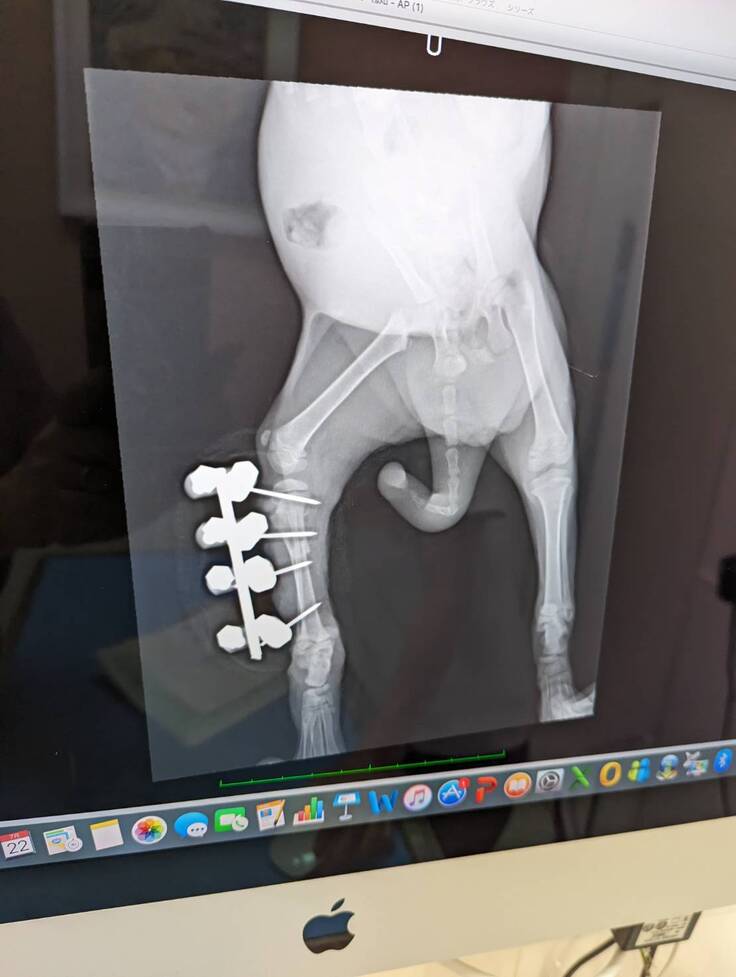

この子の保護名は‘‘マルメロ‘‘

生後1か月半の女の子です。

北海道美唄市の道路の真ん中で動けずぐったり横たわっているところを

空知総合振興局に収容され、同日に当会に保護依頼が来ました。

恐らく車にはねられたのだと思います。

検査の結果、、、

①左大腿骨と骨盤の関節が少し外れてる

②骨盤骨折

③右下腿骨骨折

小さなマルメロの下半身は多くの困難を抱えていました。

すぐに入院、右下腿骨にボルトと金属プレートで骨を固定する手術をしました。

幸い術後の経過もよく

お陰様で食欲もあり快便!

それからボルトと金属プレートを取り出す手術を終えて、

現在は元気に走り回れるようになりました!